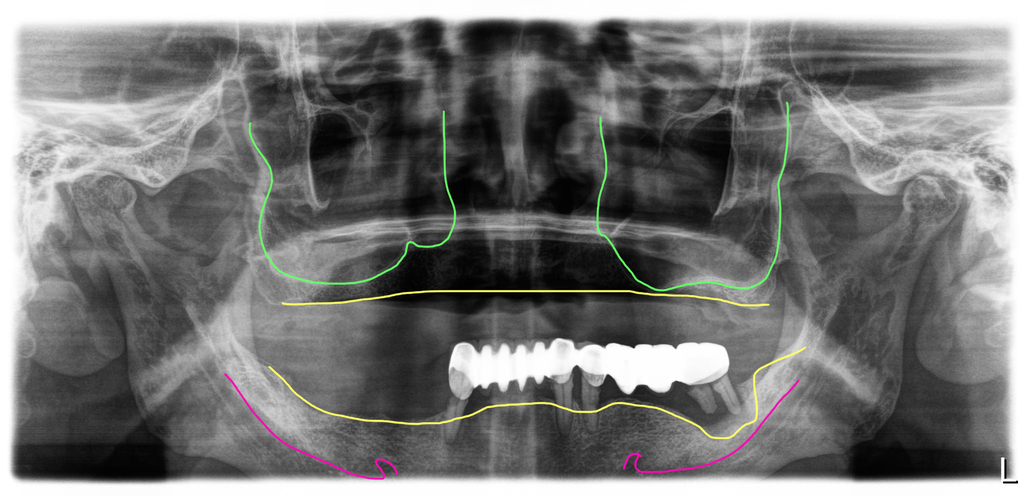

이분은 60대 남성으로 위쪽은 완전틀니 아래쪽은 브릿지와 부분틀니를 오래 사용하셨는데 아래쪽 브릿지 부분이 잇몸이 나빠져 많이 흔들리면서 불편을 느껴 치료를 시작하게 된 경우입니다.

이 분은 아래가 너무 불편해서 윗쪽은 완전틀니를 사용하시면서 아래만 먼저 수술을 원해서 진행했어요. 브릿지와 치아를 제거하고 즉시임플란트를 11개 식립하고 지대주를 연결해서 임시치아를 만들어 드렸습니다.

환자가 원래 가지고 있던 상악의 틀니가 삐뚤어져 있어서 결국 5개월 뒤에 아래 보철을 하려고 할 때 밸런스를 맞추기 위해 윗니 전체임플란트를 결정하고 수술하셨어요.

최종완성 위아래 전체임플란트를 크라운 브릿지 방식으로 완성

이 분은 위아래 충분한 개수의 임플란트를 식립해서 자연치와 가장 유사한 형태의 보철인 크라운 브릿지 방식으로 치료를 마무리한 모습입니다.

현재 이 분은 6년째 별다른 문제없이 잘 사용하고 계시고 정기검진도 잘 받고 계세요.